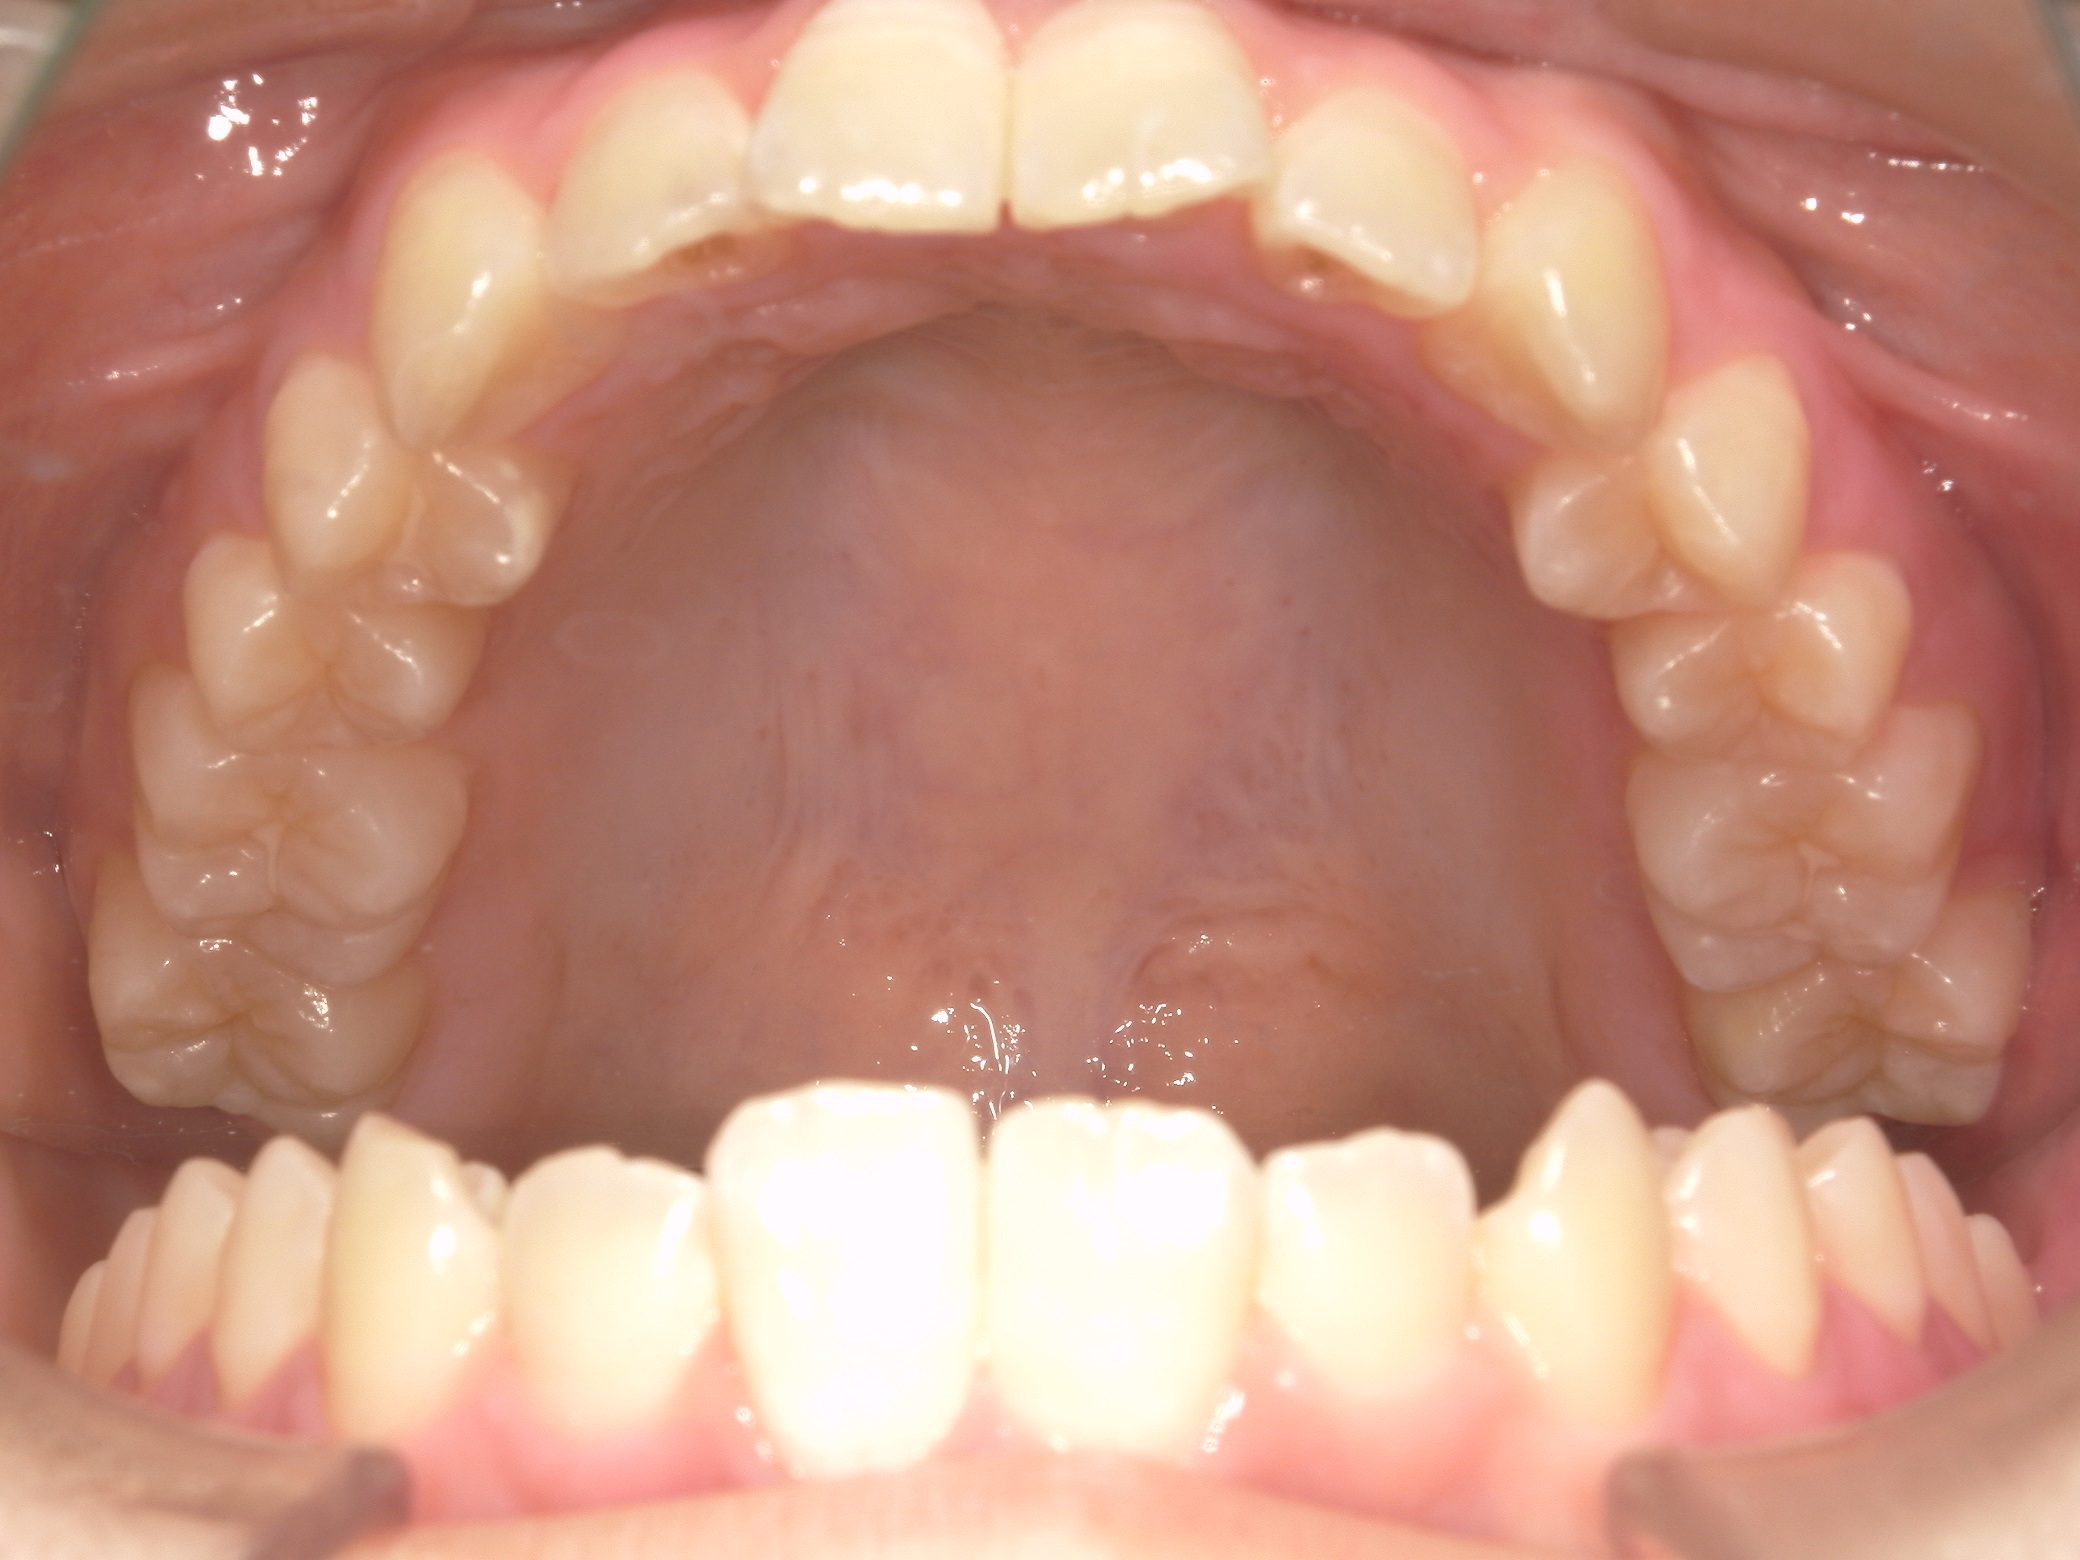

【小学生】マイオブレース矯正 受け口を改善 ①

小学生で開始

マイオブレース

受け口

1期治療のみで改善

Before

After

治療期間

1年11カ月年

治療開始

10歳

種類

マイオブレース矯正

使用装置

機能矯正装置

コメント

毎日装置の装着と MFT 口腔筋機能療法 に取り組んでくれたためスムーズに終わりました。

上顎前歯の並びをもう少し別の装置で改善することも提案しましたが、本人、保護者の方ともに

今の歯並びで満足しているということだったのでこれで終了しています。

MFTを頑張ってくれたため、お口の筋肉バランスもよく、後戻りもしていません。